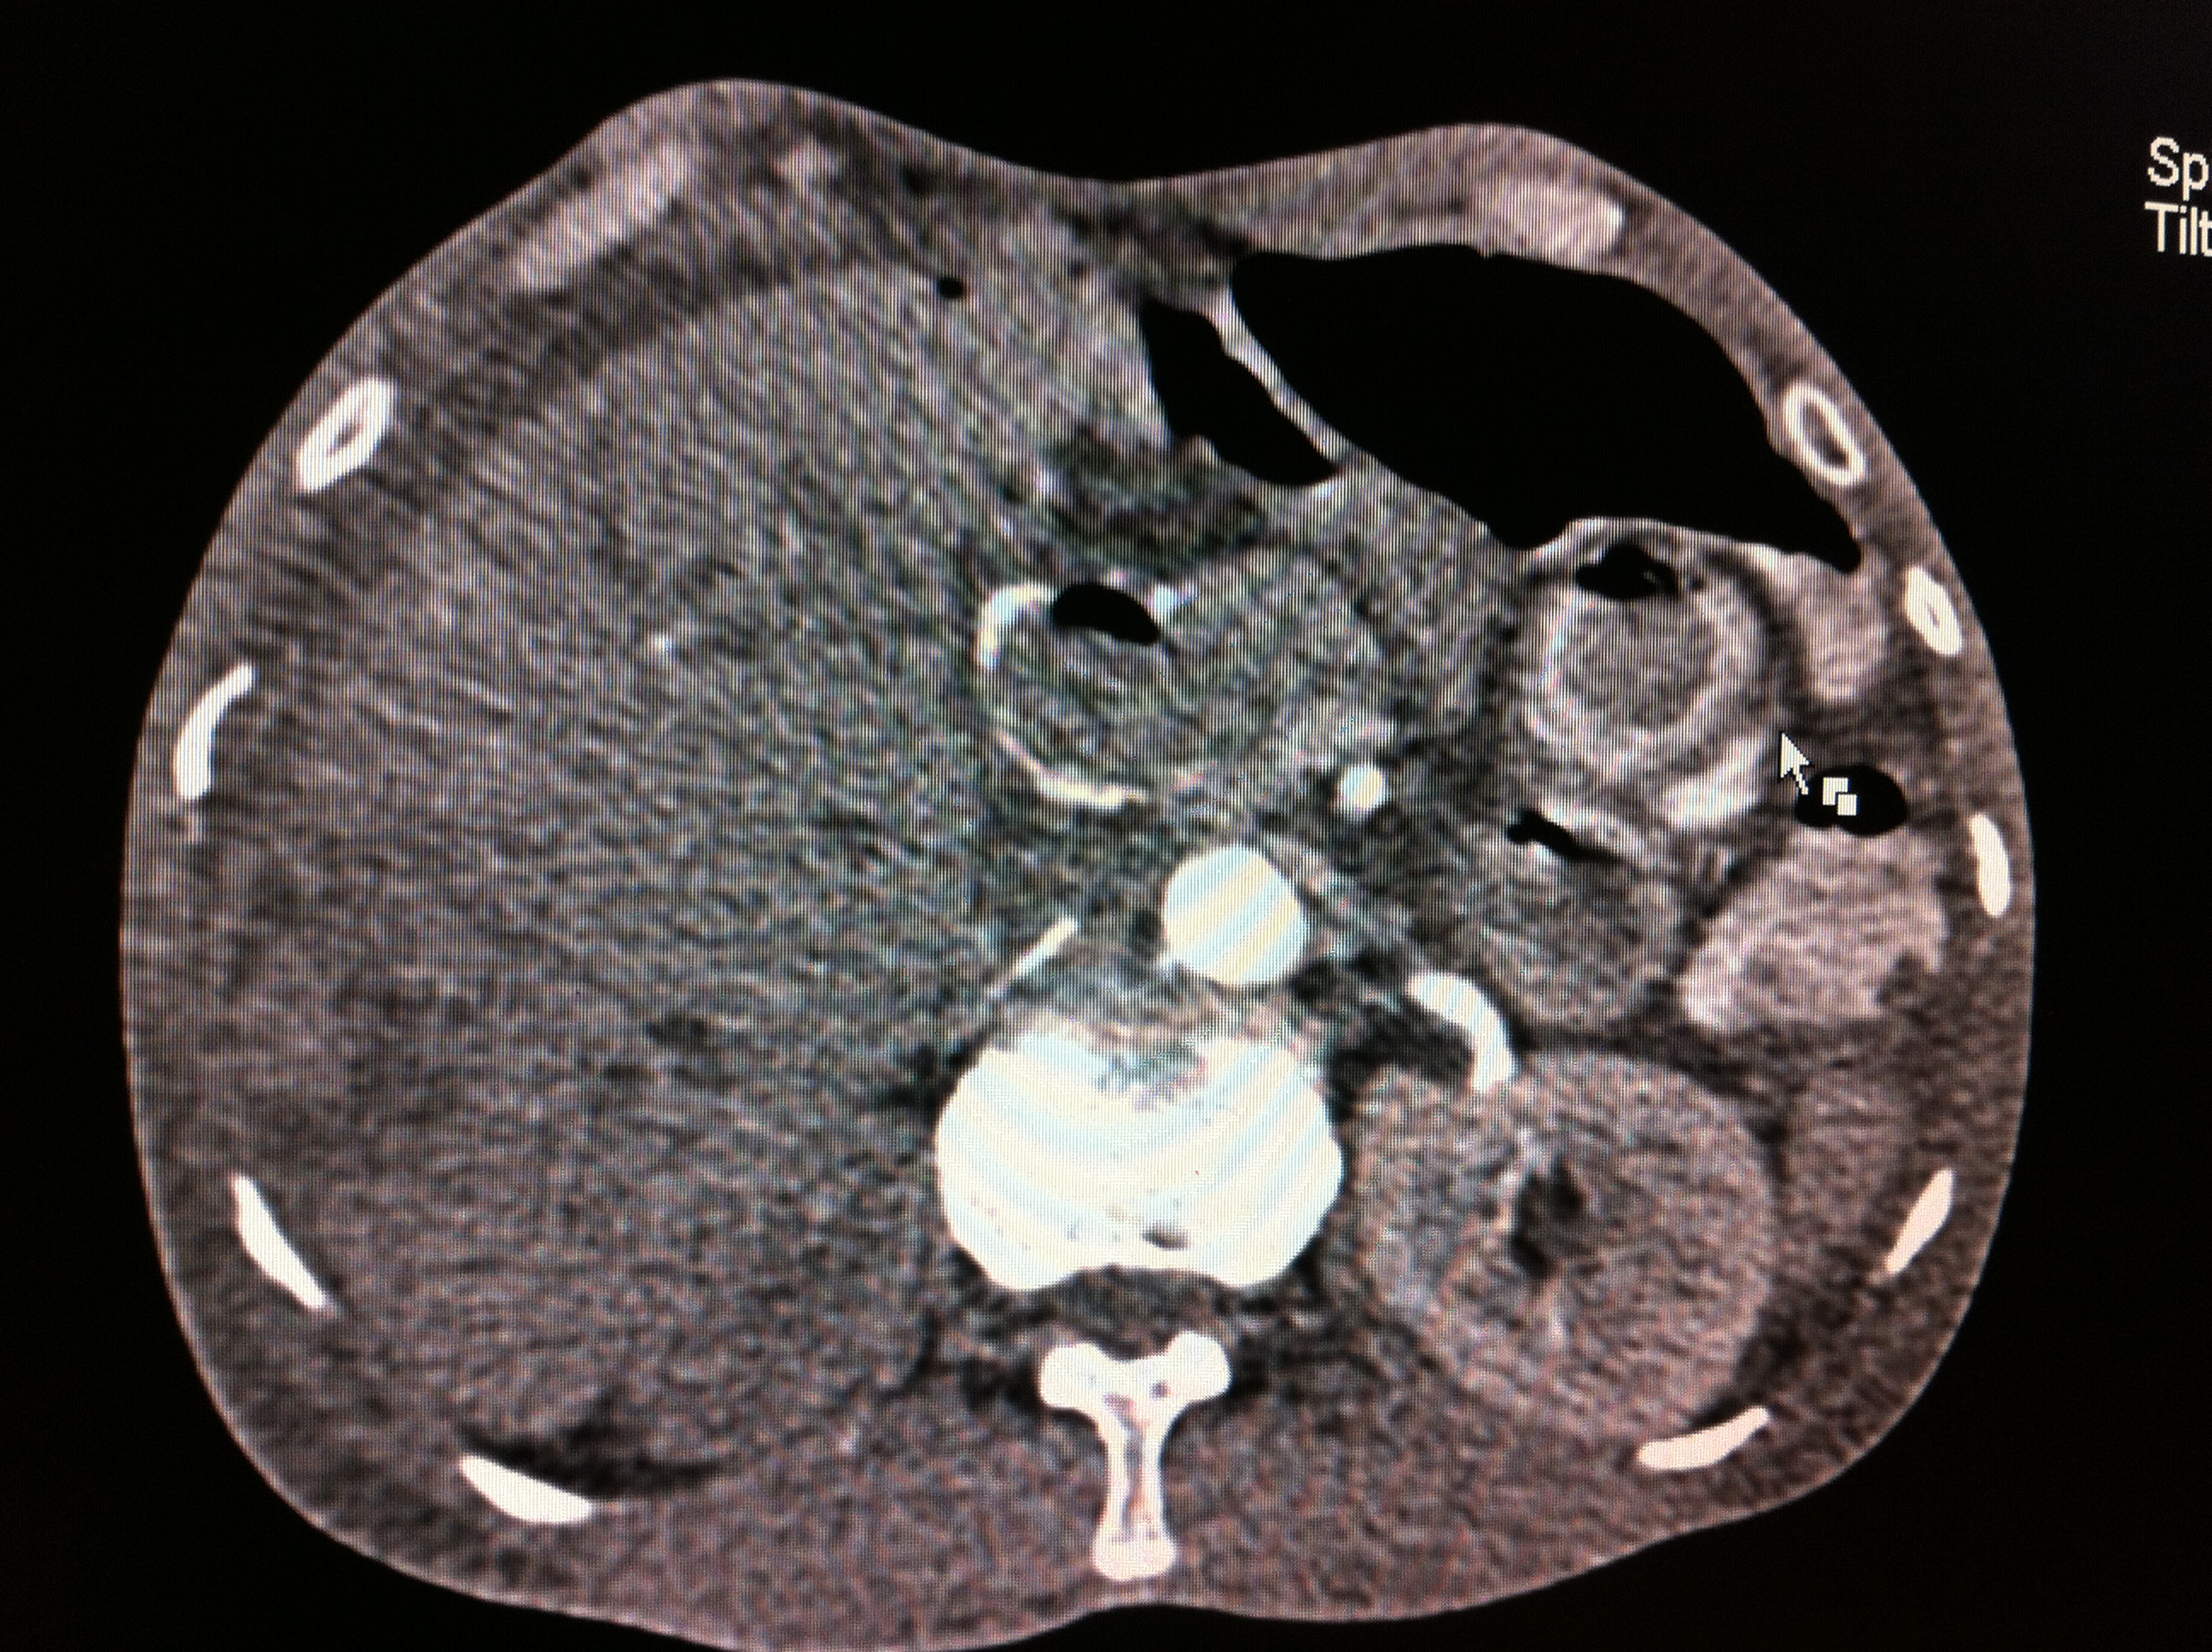

Endoscopic Retrograde Cholangio-Pancreatography (ERCP) has advantage of having bothdiagnostic and therapeutic utility and most common indication for endoscopic sphinterotomyis choledocholithiasis. Therapeutic ERCP is quite often associated with complications, mostcommon being acute pancreatitis followed by bleeding. Most common source of bleedingis small branches of pancreaticoduodenal artery (PDA) which lie close to papilla. We reporta rare case of leaking right hepatic artery pseudoanerysm following clearance of commonbile duct (CBD) stones by ERCP presenting with shock and upper GI bleed.